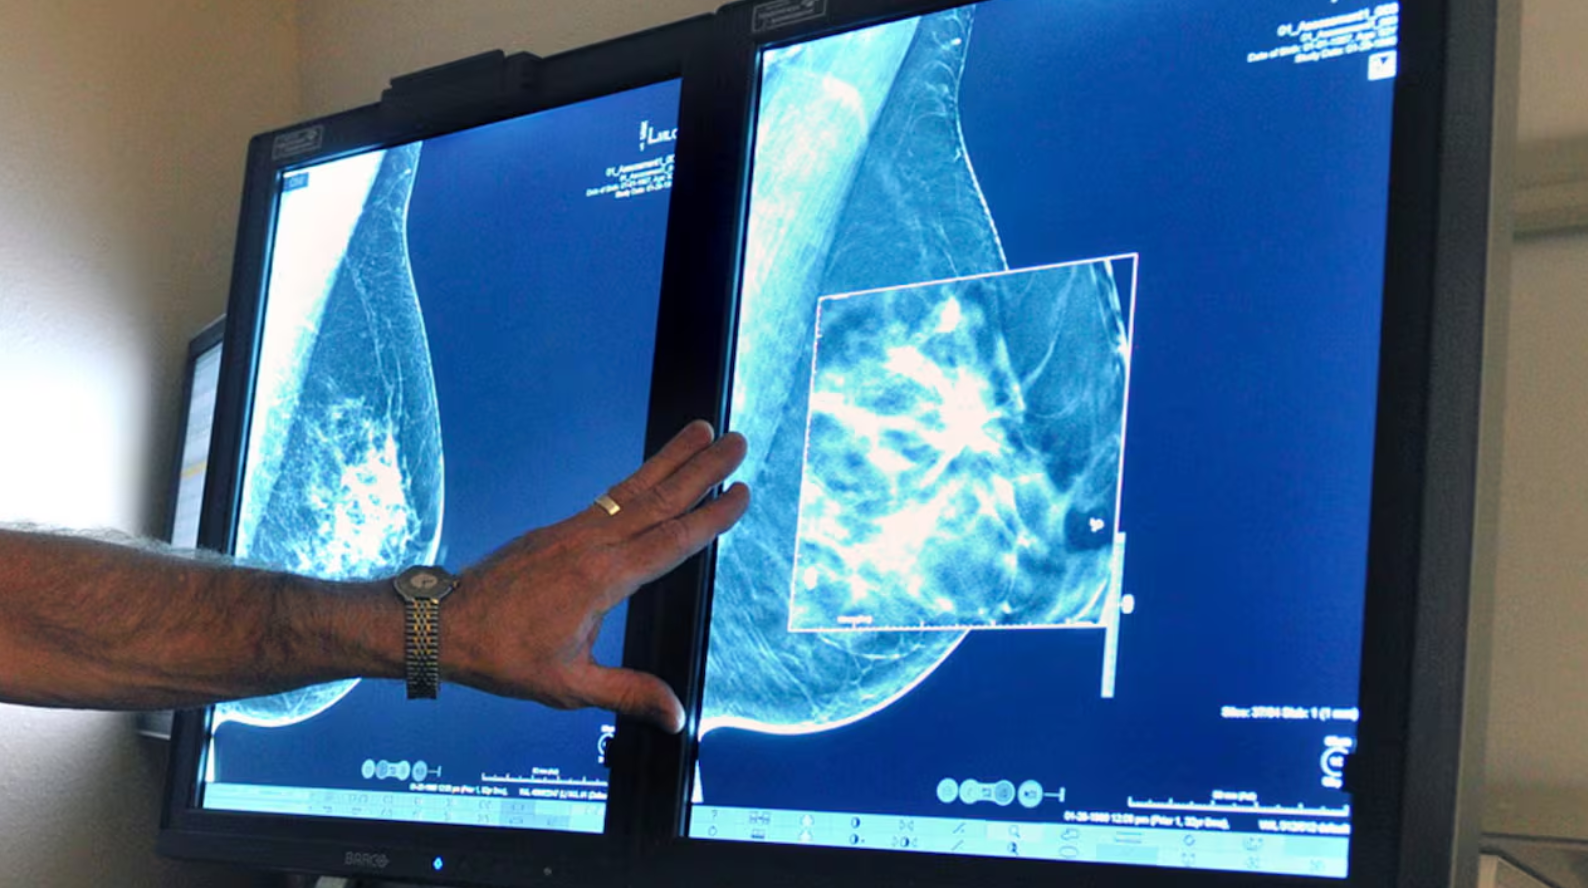

Các bác sĩ đã bắt đầu giảm chỉ định xạ trị đối với bệnh nhân ung thư vú có nguy cơ tái phát hoặc di căn thấp. Ảnh: iStock

Xạ trị từ lâu được xem là một phần quan trọng trong điều trị ung thư vú. Tuy nhiên, trong những năm gần đây, các bác sĩ bắt đầu thận trọng hơn trong việc chỉ định phương pháp này, đặc biệt với bệnh nhân có nguy cơ tái phát hoặc di căn thấp.